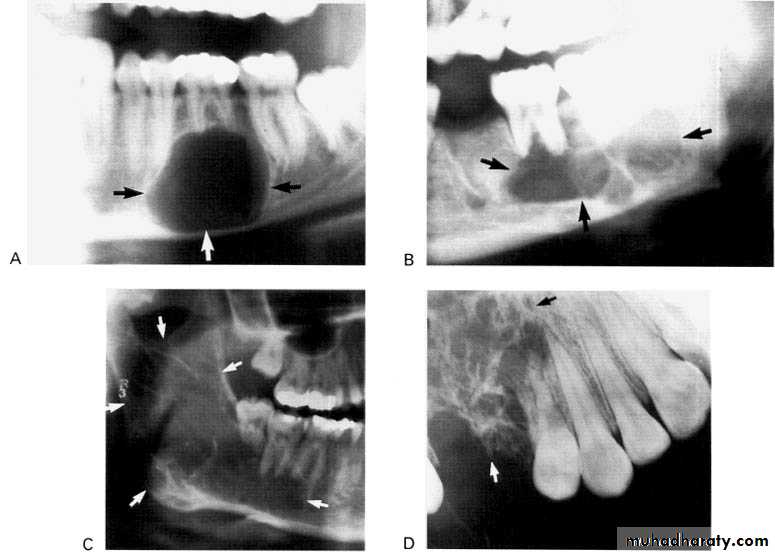

A: Radiolucent apical scar left after successful endodontic treatment..

B:New bone forming from the periphery of theLesion.

If the R.L.enlarged, pain,sinus,or no regression in the size of lesion after 6months (P. A. Cyst).

Apical scar